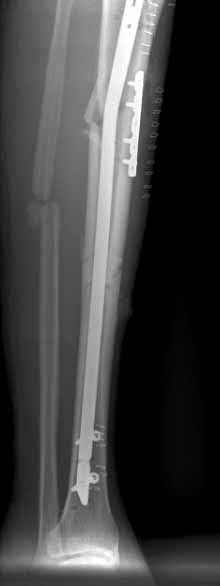

These can be challenging. I agree w/ all Dr. Carr's points. My preference to prevent the deformity is to use an anteromedial plate. See attached case.

![]() |